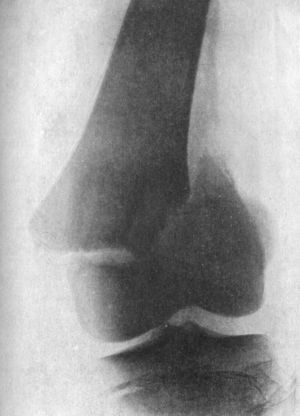

| 138. | Radiogram of Case of Double Genu Valgum in a Child | 268 |